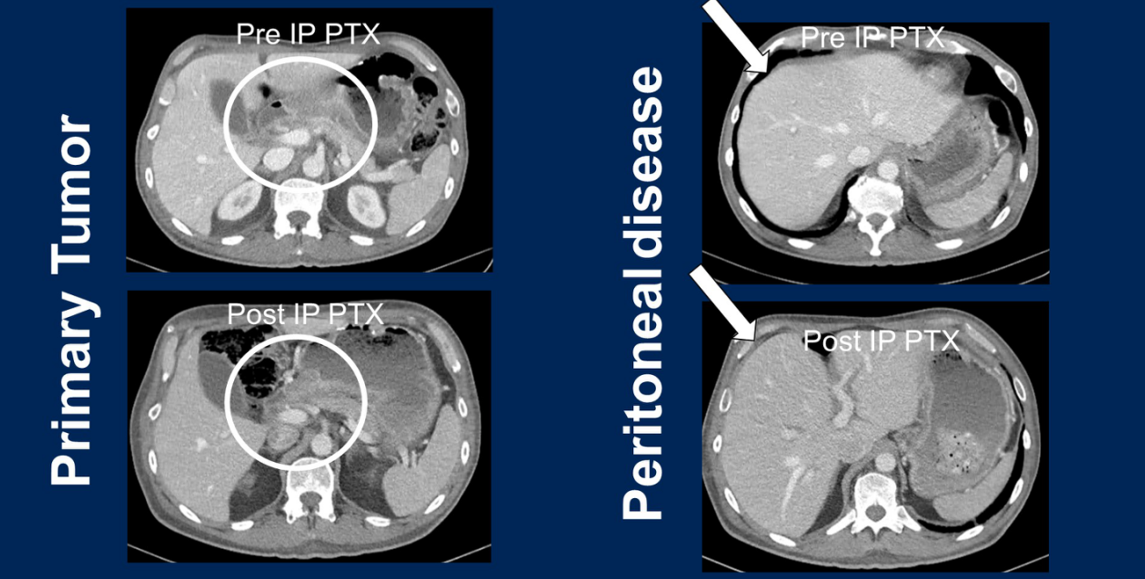

在这一原则指导下,一名腹膜转移患者幸运地入组了STOPGAP研究(一项旨在评估双向紫杉醇治疗胃癌腹膜转移安全性和有效性的Ⅱ期临床试验)。该研究要求患者在接受至少3个月的一线系统治疗且无进展后方可入组。本例患者为HER2阳性(IHC 3+)且CPS高表达(CPS 31),在接受静脉联合腹腔灌注紫杉醇的同时,序贯应用了曲妥珠单抗、帕博利珠单抗及氟尿嘧啶。治疗后的影像学对比显示,患者的远端胃原发灶持续缓解,肝周及脾周的恶性腹水完全消失。